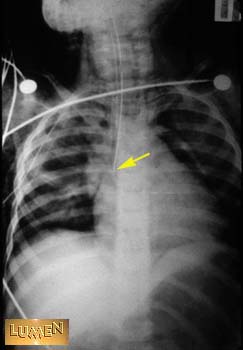

Where is the tip?

Answer

Right main bronchus.